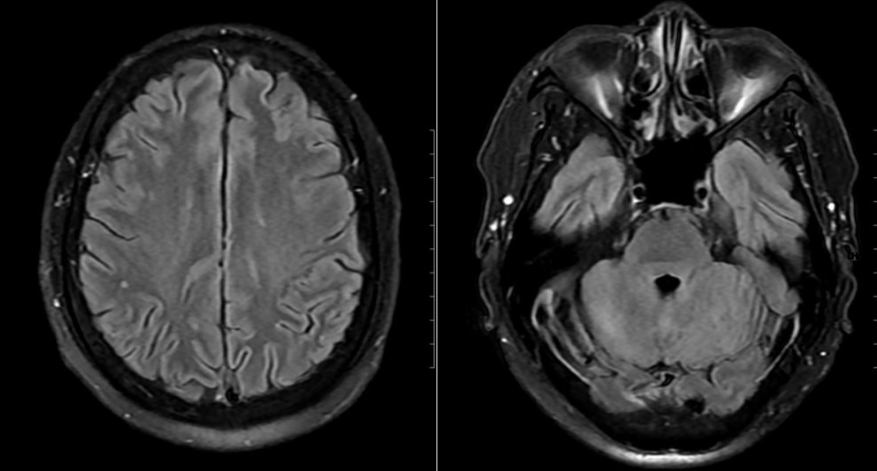

Mặc dù chưa có biểu hiện thần kinh rõ ràng, bệnh nhân vẫn được chọc dò dịch não tủy để loại trừ biến chứng. Kết quả cho thấy dịch não tủy tăng tế bào và protein, phản ứng Pandy dương tính, xác định tình trạng viêm não – màng não. Hình ảnh MRI sọ não còn phát hiện ổ tổn thương nhỏ tại thùy chẩm trái.

Hình ảnh não bệnh nhân có tổn thương.

Sau 24 giờ, bệnh nhân cắt sốt, thể trạng cải thiện rõ. Sau 15 ngày điều trị tích cực, các xét nghiệm và hình ảnh học cho thấy tổn thương hồi phục hoàn toàn, bệnh nhân xuất viện trong tình trạng ổn định, không để lại di chứng thần kinh.